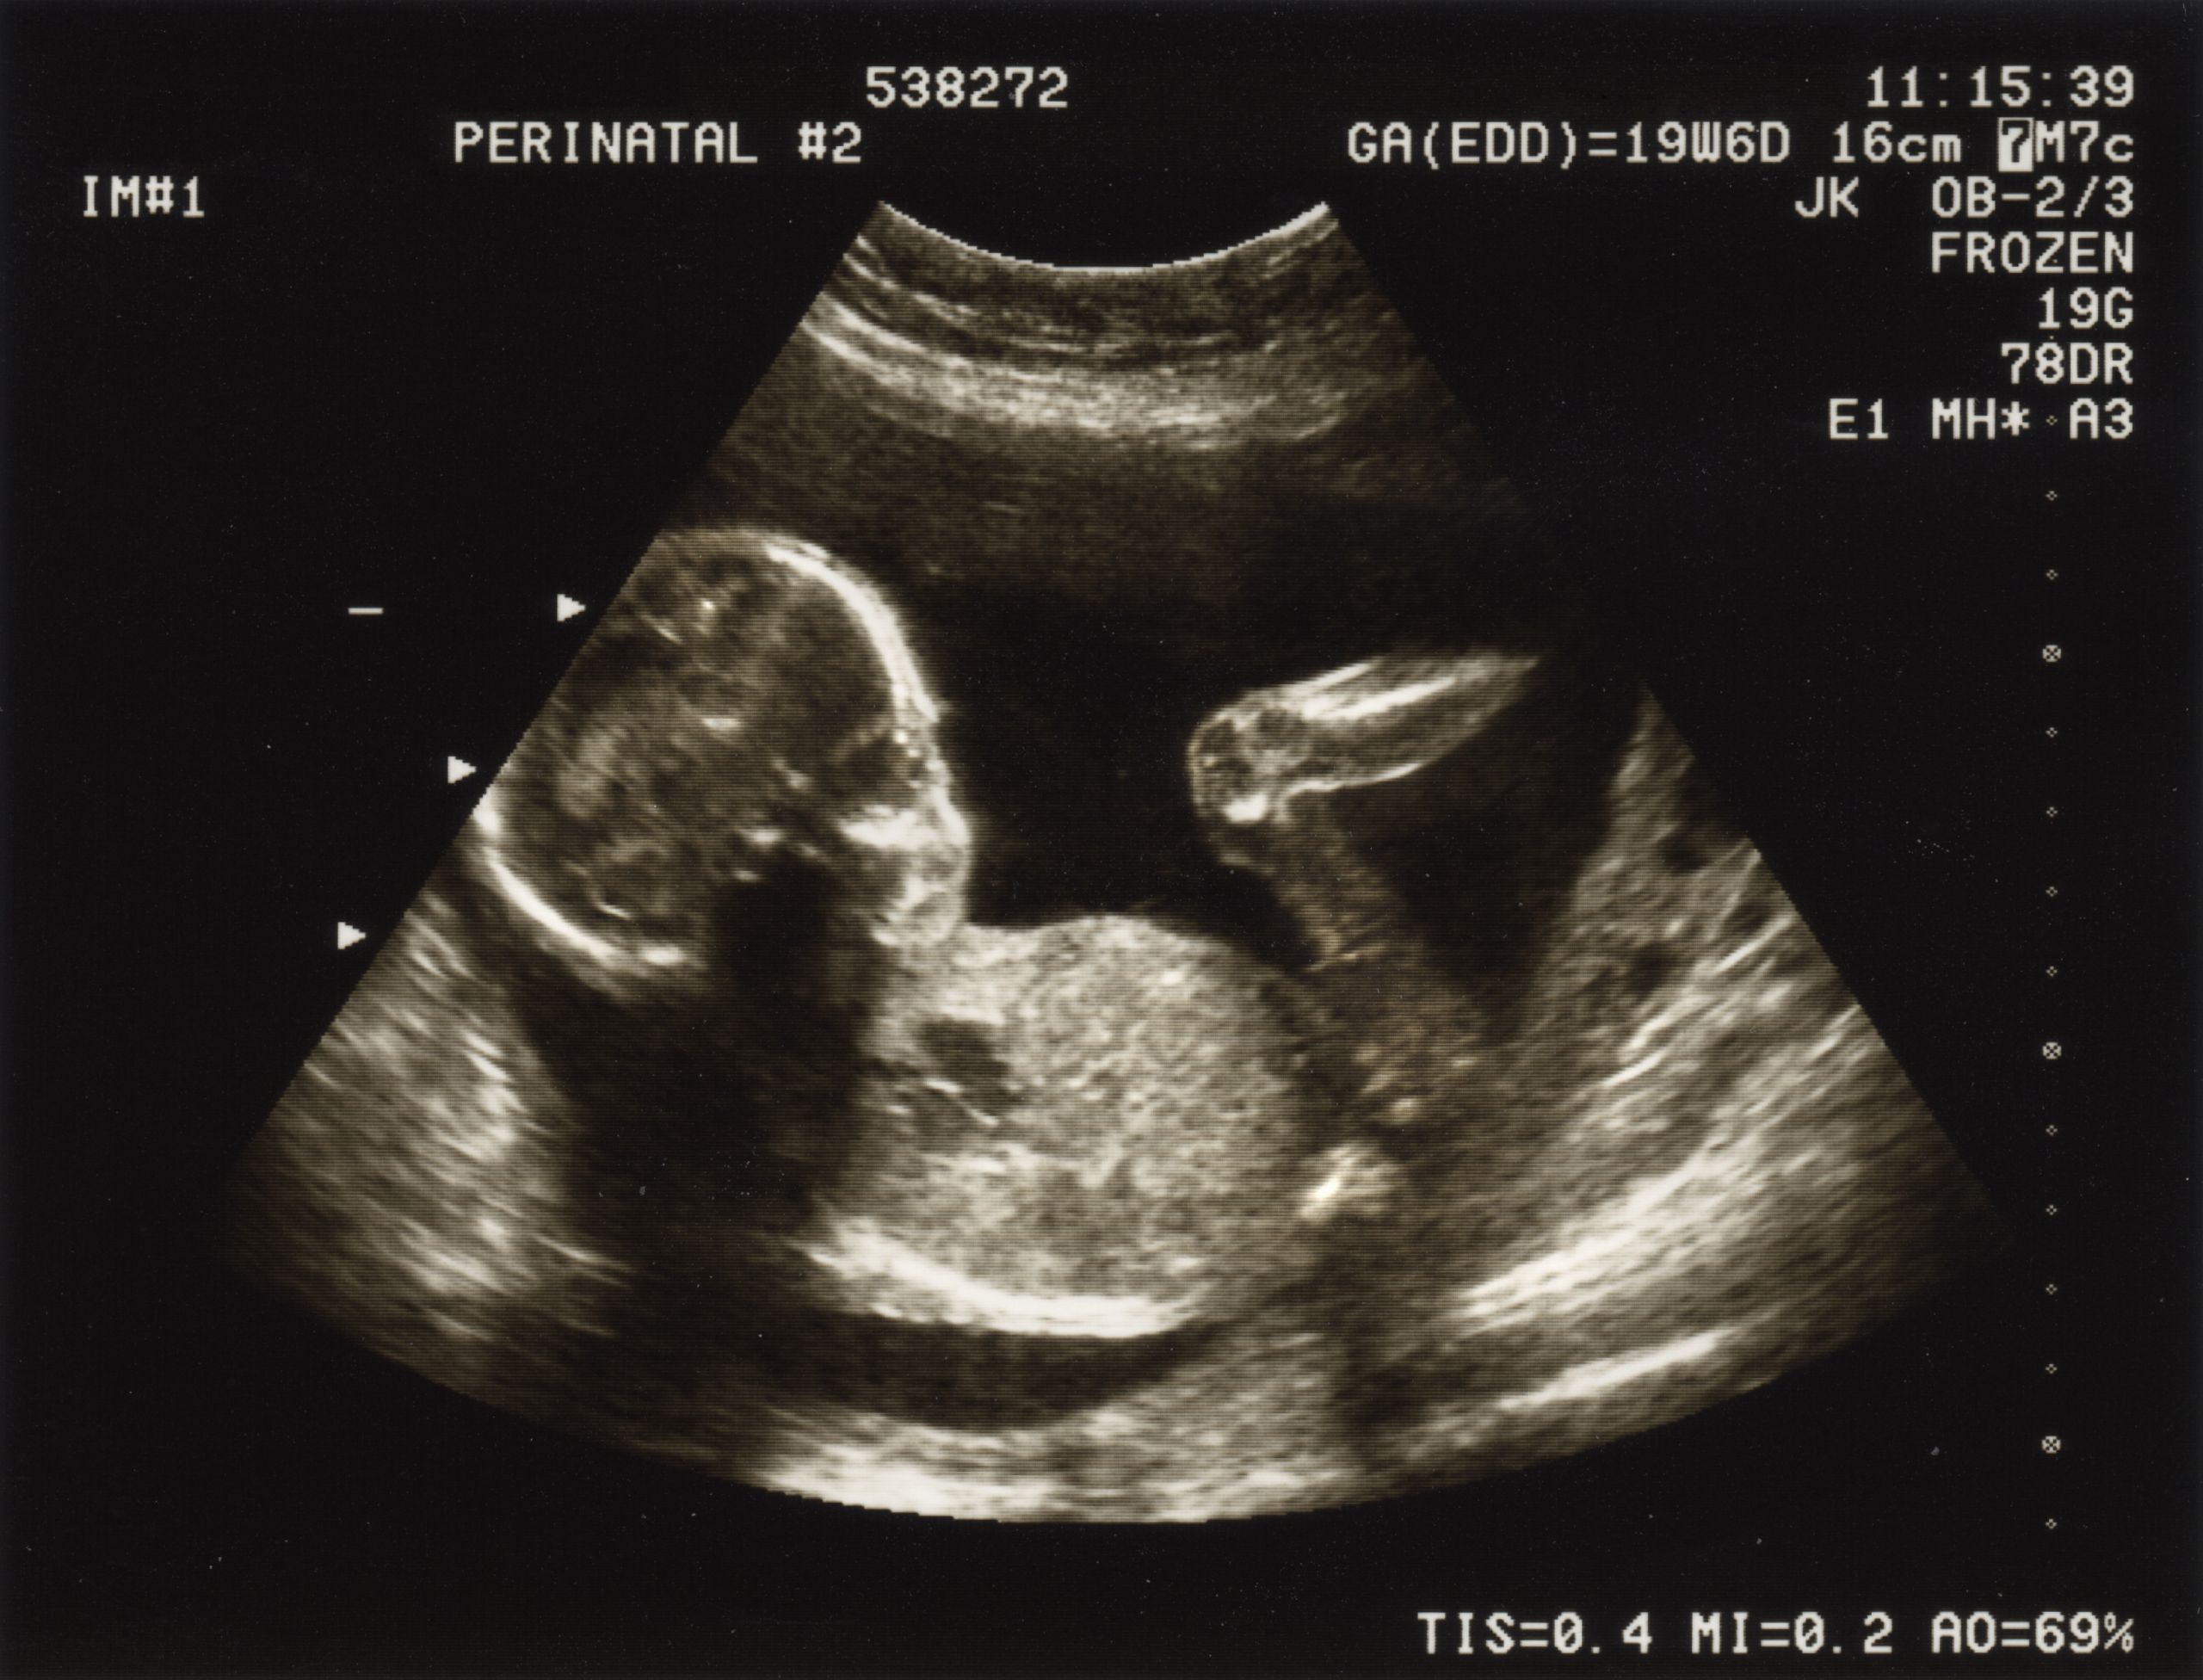

Boardul național reprezintă o structură multidisciplinară de sprijin, coordonată la nivel național, care are ca scop evaluarea și managementul sarcinilor cu risc major și patologie fetală severă. Este format din experți în medicină materno-fetală, cardiologie fetală, neonatologie, genetică, anestezie și chirurgie pediatrică.

Exemple de patologii gestionate în cadrul Boardului

01. Sarcini gemelare monocorionice complicate cu TTTS (Twin-to-Twin Transfusion Syndrome) și TAPS (Twin Anemia Polycythemia Sequence) – cazuri ce pot necesita ablație laser fetoscopică.

02. Anomalii fetale multiple sau complexe – unde este necesară o strategie integrată de evaluare și planificare postnatală.

03. Hernia diafragmatică congenitală – poate beneficia de procedura FETO (fetoscopic endotracheal occlusion) pentru creșterea șanselor de supraviețuire.

04. Sarcini cu anemie fetală severă – cu indicație de transfuzii intrauterine.

05. Obstrucții de căi urinare fetale – cazuri selectate pot fi gestionate prin shunt vezico-amniotic

06. Patologie cardiacă fetală – de la defecte structurale majore până la aritmii fetale severe, cu implicarea cardiologului pediatric și a chirurgului cardiovascular.